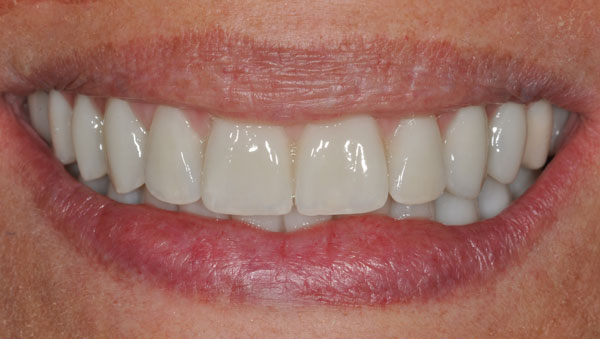

Alcuni casi clinici risolti con l'Implantologia (prima e dopo)

Vedrai le foto di decine di casi simili al tuo, brillantemente risolti